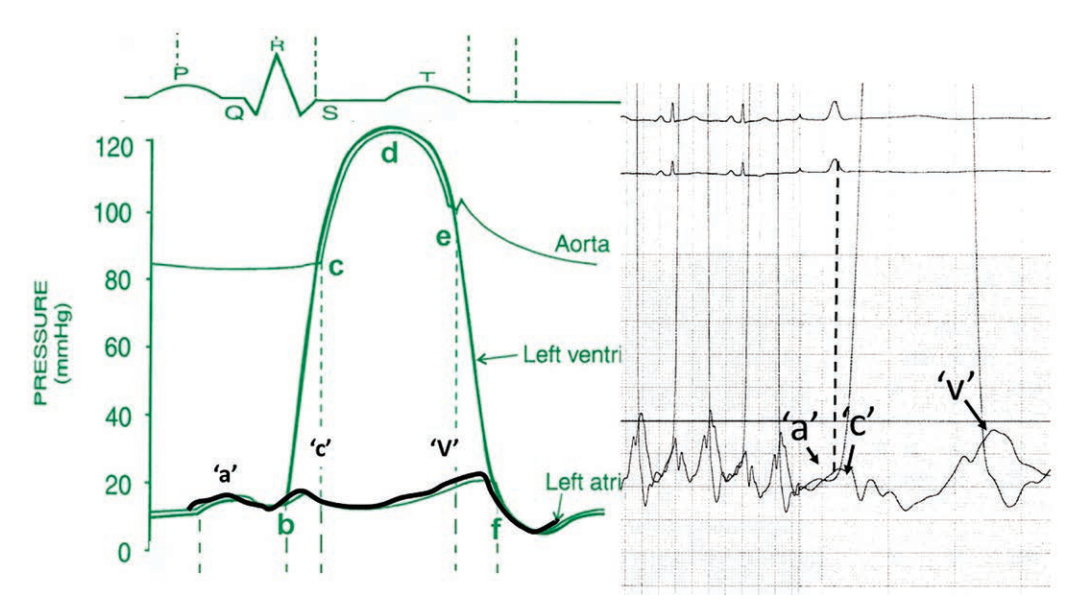

The famous Charles Wiggers diagram (Figure 3) describes normal cardiac pressures over the cardiac cycle corresponding to the electrocardiogram (ECG) (top of Figure 3). The LA pressure waveform normally demonstrates three waves representing three phases of the cycle: atrial systole (‘a’), ventricular contraction generating the ‘c’ wave, and the atrial filling ‘v’ wave. Clinically, in the cath lab, we often superimpose the pulmonary capillary wedge (PCW) (or LA) pressure over the simultaneous LV pressure tracing to assess mitral valve hemodynamics, either regurgitation or stenosis. As a reminder, the left ventricular end diastolic pressure (LVEDP) occurs at the end of ‘a’ wave and can be marked by a line from the ECG ‘r’ wave (Figure 3, right side, dotted line). Notably, because the LVEDP includes atrial contraction rather than only passive filling, in certain states, it can significantly exceed the PCW or mean LA pressure.